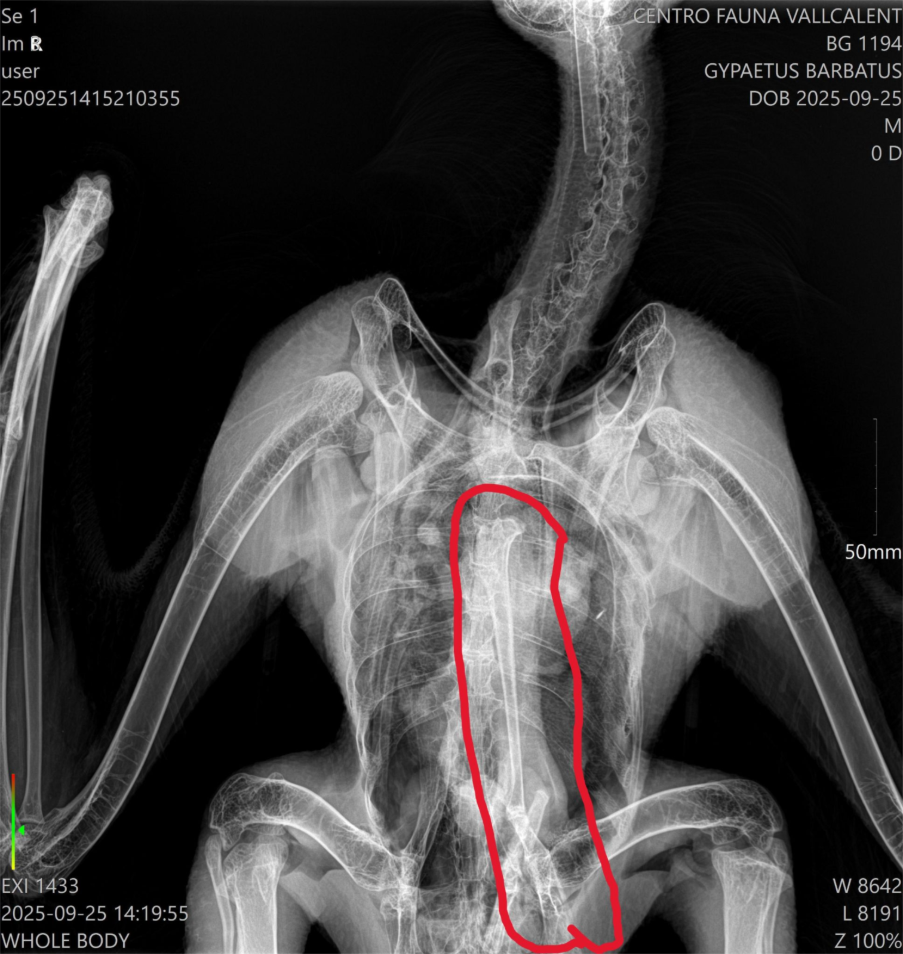

Poaching strikes again. The latest known victim of this serious wildlife crime is a Griffon Vulture in France at the Cévennes National Park. Following the discovery of a carcass, experts performed a necropsy and toxicological analysis on the Griffon Vulture, with the X-ray revealing that twenty lead shot pellets riddled its body.